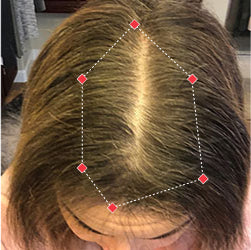

Indications for Use

The iRESTORE Hair Growth System Elite is indicated to promote hair growth in males who have Norwood-Hamilton Classifications of IIa to V and in females who have Ludwig-Savin Classifications I to II, and in both with Fitzpatrick Skin Phototypes I to IV. In other words, iRESTORE is not intended for people who are bald or have advanced hair loss.

Laser therapy works to reactivate thinning and dormant hairs. For completely bald areas of the scalp, there may be no way to promote hair regrowth. If you still have hair follicles, laser therapy may be beneficial to you.

Not sure? Email us to have our specialists evaluate your scalp conditions to see if iRESTORE is suitable for you.